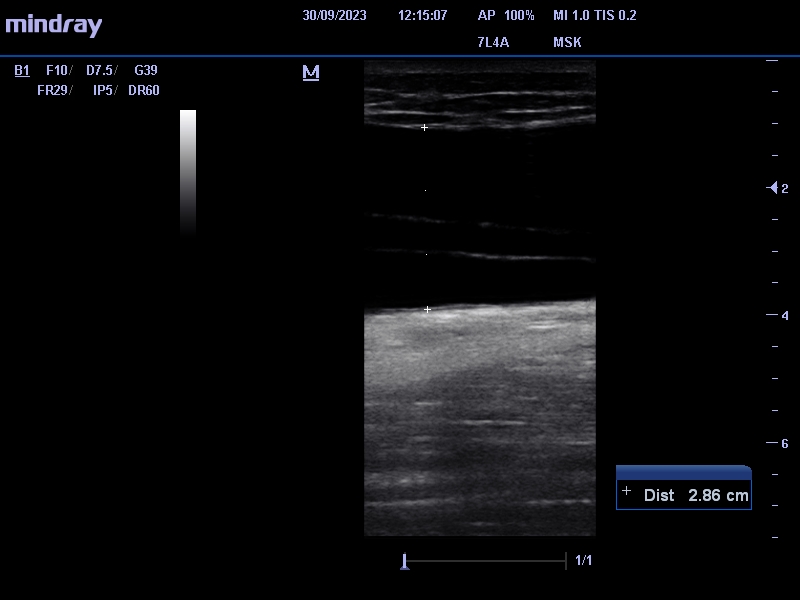

Se identifica entre el tejido celular subcutáneo y la fascia muscular, colección anecogénica, avascular de 2,8 x 17 cm (antero-posterior x craneocaudal) que nos sugiere lesión de Morel-Lavallée.